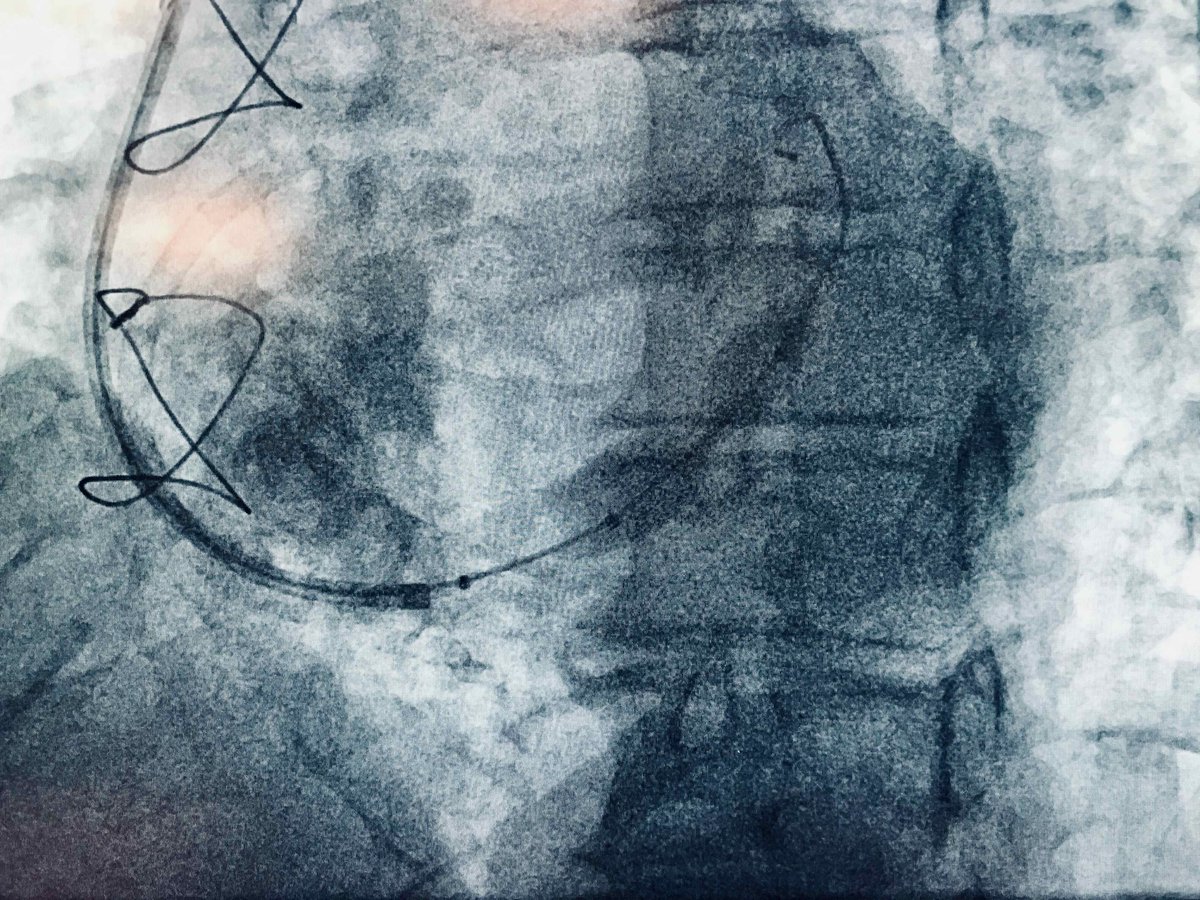

Another barrier bites the dust! On Feb 28, 2024 we did 1st TDADR: presumably 1st case outside 🇯🇵 Successful reentry w/ CP12 using HD-IVUS after failed Stingray ADR. Credit to @Laserrman (my mentor!) for sharing knowledge on IVUS 3D wiring. @tadano98 @SKuramitsu0511 @nikardiologii

9

18

62